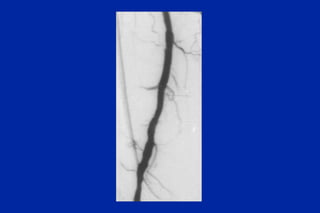

Este documento resume los principales tipos y técnicas de angiografía. Describe brevemente la angiografía, arteriografía, flebografía y linfografía, así como las técnicas de contraste y materiales utilizados. También explica los principales accesos vasculares, la técnica de Seldinger, la angiografía por sustracción digital y algunas técnicas endovasculares comunes.